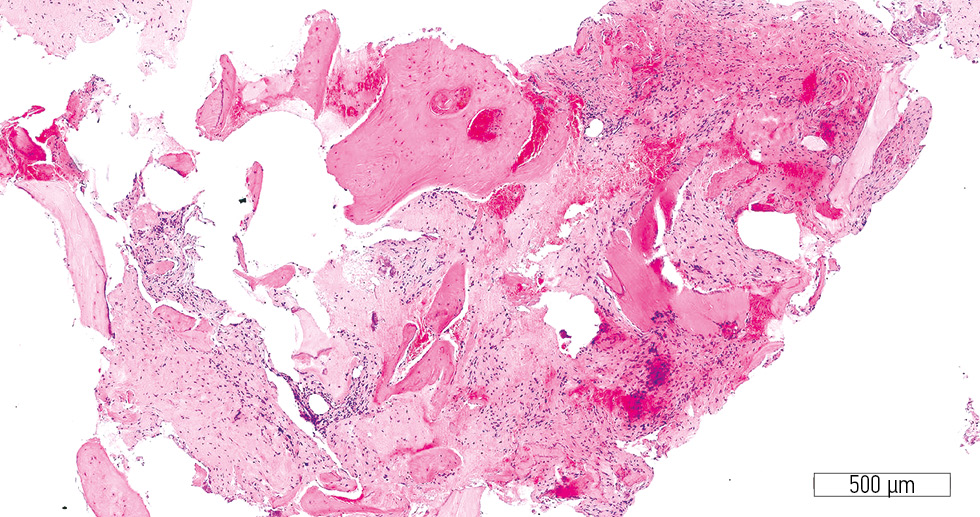

Microscopic evaluation after 4 months revealed substantial differences in the histological architecture of the regenerated bone between the treatment and control groups. In the treatment group, a well-developed stromal component and newly formed bone trabeculae were observed (Fig. 1). The stromal component consisted of densely packed mesenchymal cells with a minimal number of blood vessels per mm2 (Fig. 2). Areas of osteogenesis contained active osteoblasts, and the newly formed bone lamellae showed multiple lacunae, some with osteocytes and isolated osteoblasts (Fig. 3).

Fig. 1. Well-developed stromal component (treatment group). Hematoxylin-eosin stain; original magnification ×100.